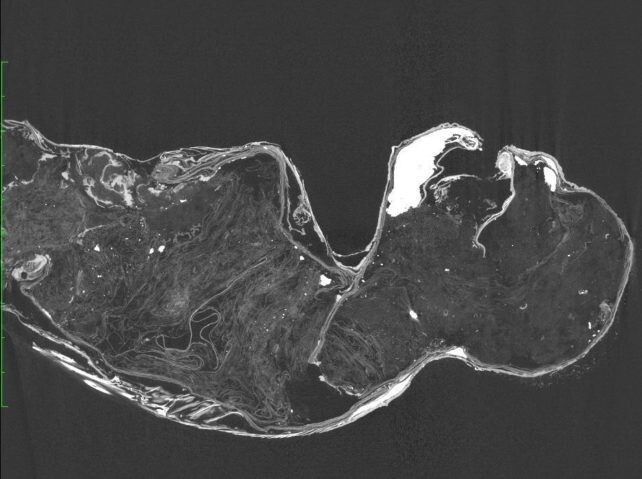

Это разрешение было им дано и они занялись исследованием высушенного существа в феврале 2022 года. Учёные провели визуальный осмотр, сделали рентген, компьютерную томографию, анализ ДНК, изучили объект с помощью электронного микроскопа и радиоуглеродного датирования.

Первое, что бросилось им в глаза, — это полное отсутствие скелета в верхней части существа. Обычно фальшивые мумии русалок, эти жутких Франкенштейнов, мастерили, соединяя останки обезьян и рыб. Но в этом случае можно было говорить только о хвосте рыбы, там скелет имелся. А наверху-то что?

Сканирование показало, что объект сделан из ткани, хлопка и бумаги, покрытых смесью пасты из древесного угля и песка. Голова в основном состоит из хлопка и покрыта чем-то вроде гипса. Волосы на голове — шерсть животных, а чешуя — от двух видов рыб. Верхняя часть тела покрыта кожей рыбы-фугу, а нижняя — чешуей одного из видов горбыля. Ногти на пальцах рук сделаны, по всей вероятности, из рога животного, а челюсть с острыми зубками раньше принадлежала какой-то плотоядной рыбе.